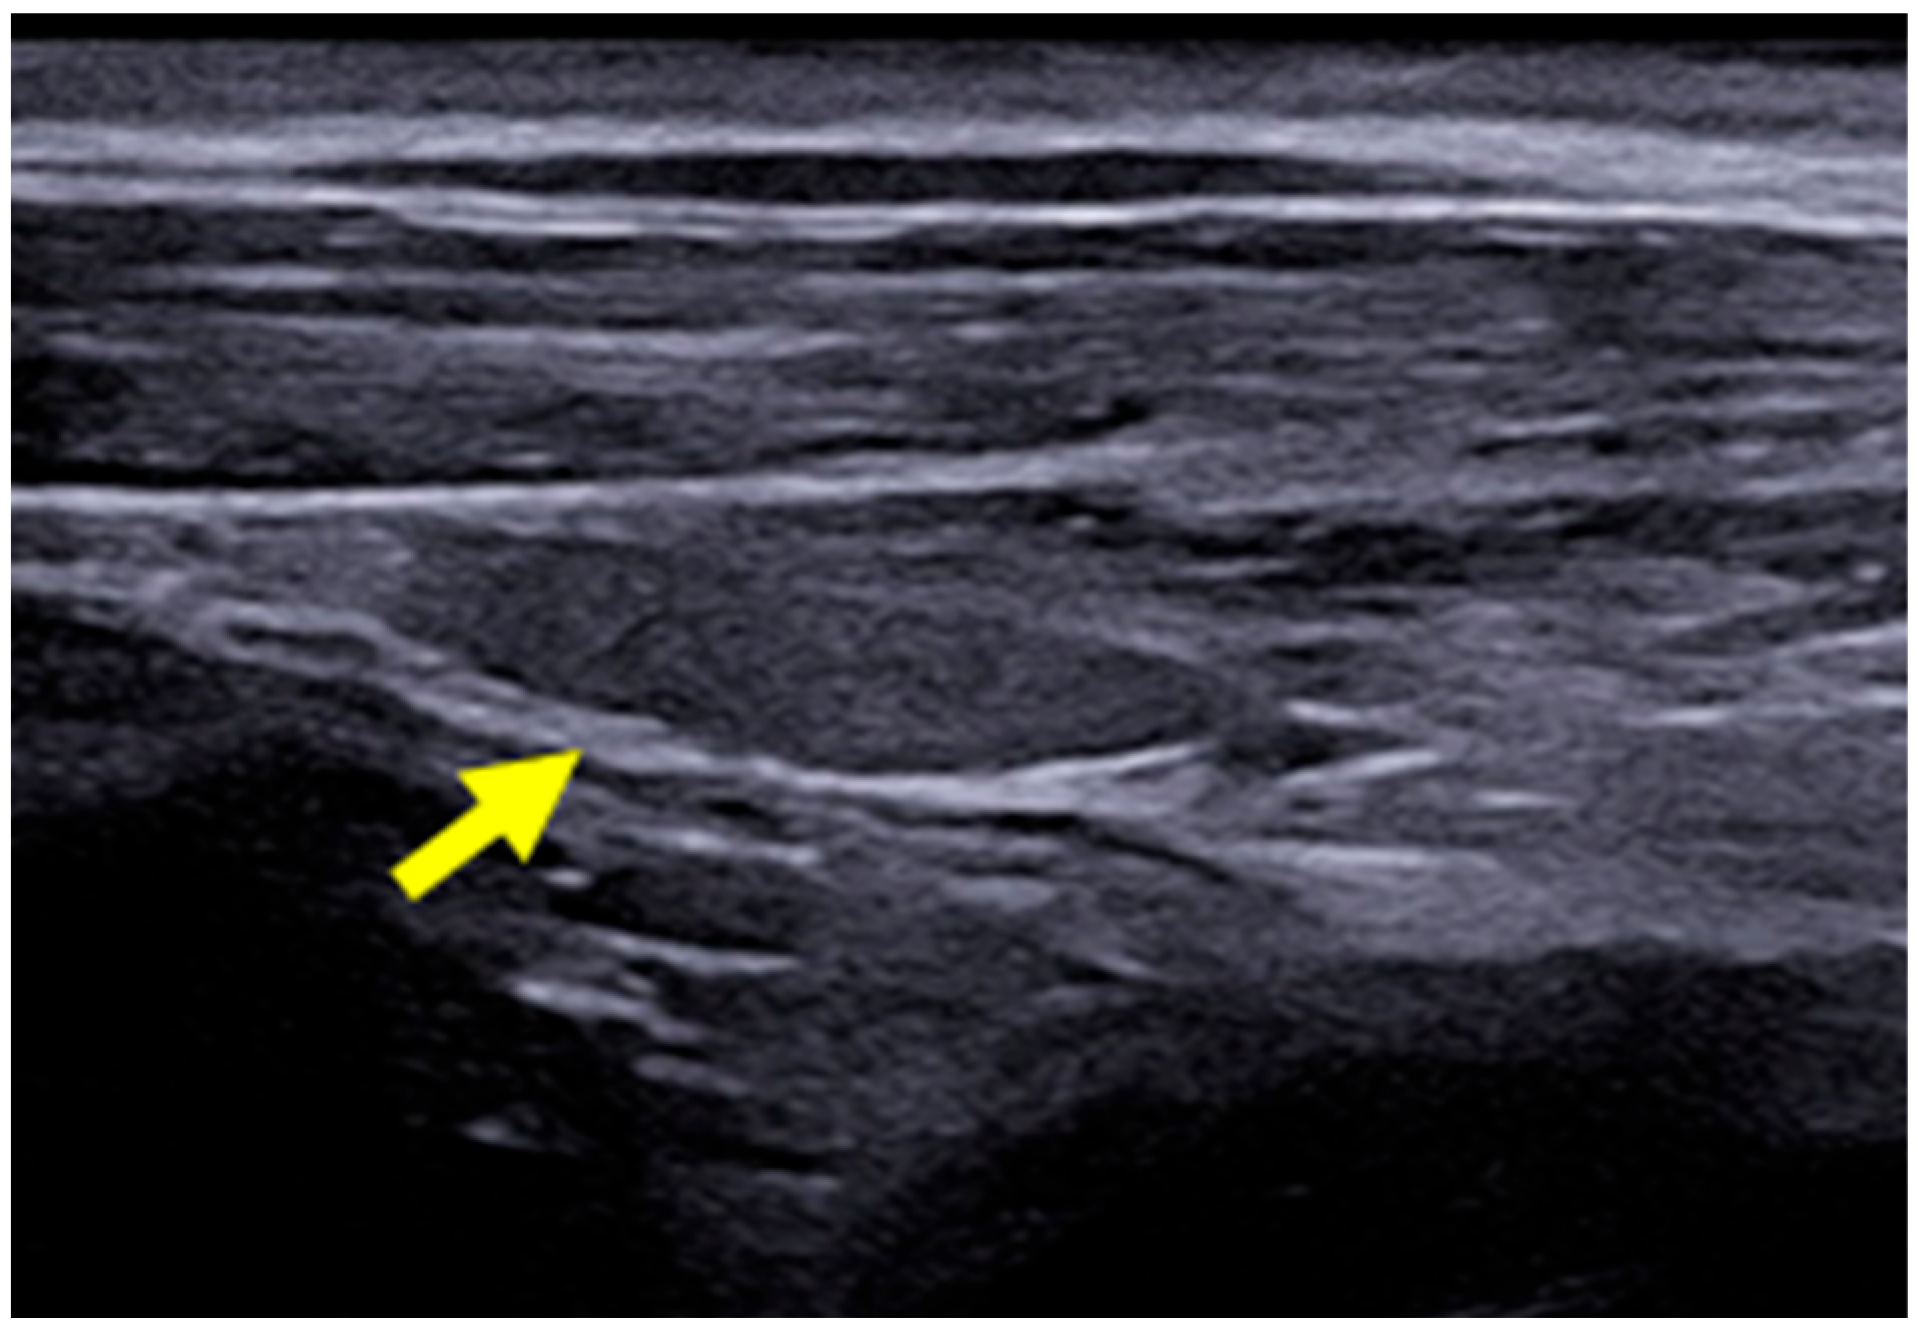

2.3. B-Mode Thyroid Ultrasonography

The B-mode ultrasound study of the thyroid was performed using the MyLabTM X8 Platform equipment (Esaote, Firenze, Italy), with a 4–15 MHz multi-frequency and linear transducer. The settings for gain, frequency, focus, time gain compensation (TGC), and depth were adjusted according to the physical characteristics of each dog participating in the study. The lobes of the thyroid gland were identified in their typical location, situated between the sternocephalic and sternothyroid muscles, ventral to the trachea and caudal to the larynx. Both were evaluated in a longitudinal manner with regard to their dimensions (length and width) and echogenicity in relation to the adjacent muscles (hypoechoic, isoechoic, or hyperechoic) and surface regularity. The aforementioned characteristics were also assessed in the transverse section, except for the dimensions (Figure 1). Figure 2 presents the right thyroid lobe on B-mode ultrasound in a longitudinal section of a female dog.

Figure 1. The B-mode ultrasound image of the right (yellow arrow) and left (blue arrow) thyroid lobes of a 9-year-old female dog.

Figure 2. B-mode ultrasound images of the right thyroid lobe of a 3-year-old female dog (yellow arrow).